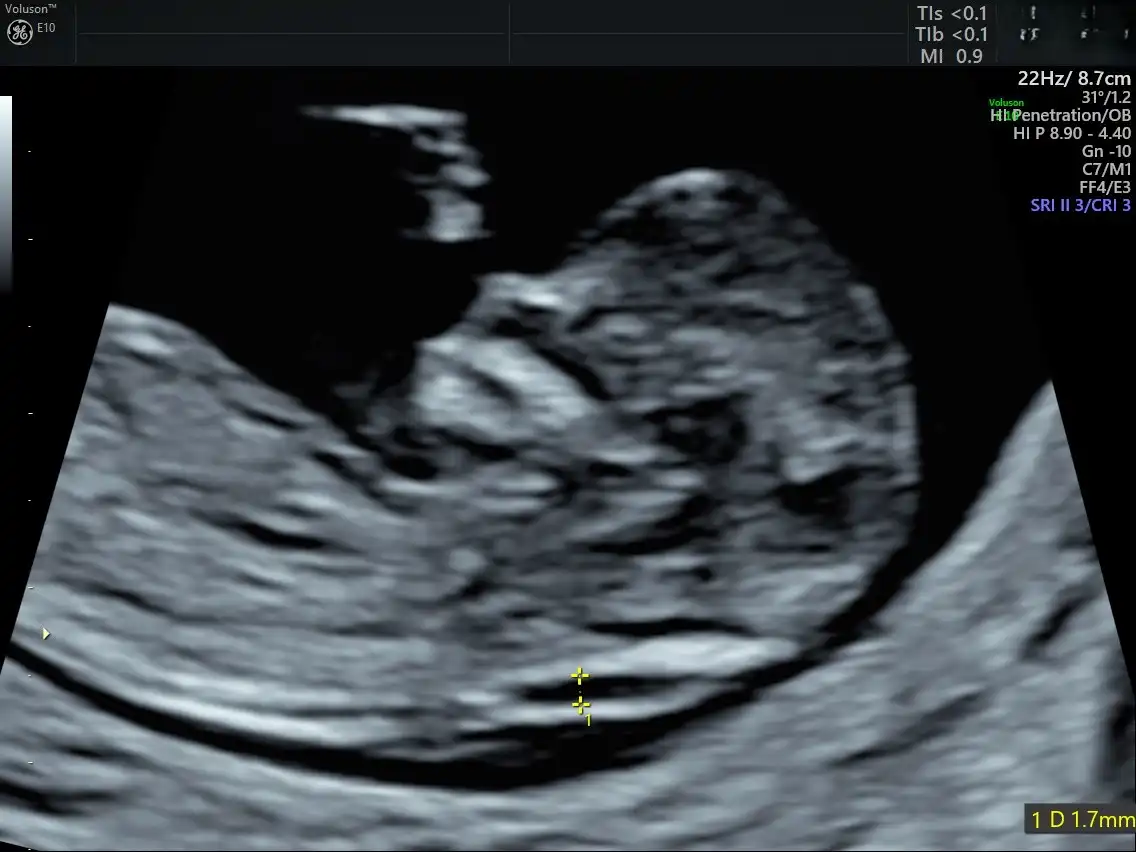

Το Voluson E10 BT19 αποτελεί την αιχμή της τεχνολογίας στην προγεννητική απεικόνιση, προσφέροντας εξαιρετική ευκρίνεια εικόνας, προηγμένη 3D/4D απεικόνιση και υψηλή ταχύτητα επεξεργασίας.

Με εξειδικευμένα εργαλεία για τον προγεννητικό έλεγχο και την καινοτόμο τεχνολογία HDlive™, επιτρέπει λεπτομερή και ρεαλιστική απεικόνιση του εμβρύου, ενισχύοντας τόσο τη διαγνωστική ακρίβεια όσο και την εμπειρία των γονέων.

Η χρήση αυτού του υπερηχογράφου είναι καθοριστική για την έγκαιρη ανίχνευση πιθανών ανατομικών ανωμαλιών και τη σωστή παρακολούθηση της κύησης, ενώ ταυτόχρονα προσφέρει μεγαλύτερη ασφάλεια και άνεση στη μητέρα και τον συνοδό της.